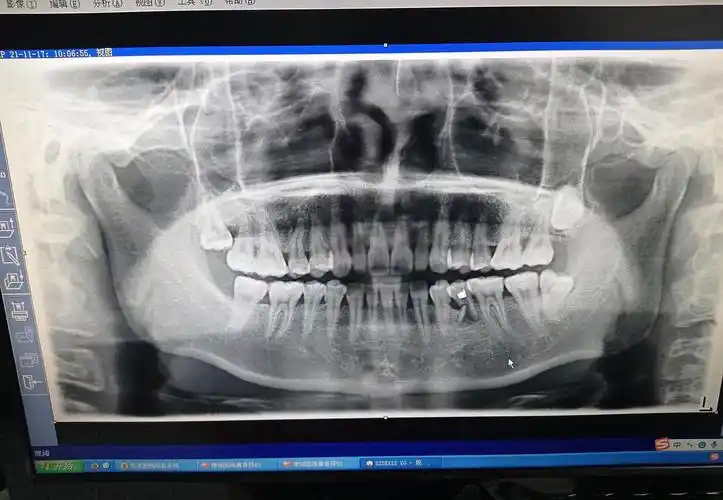

看看我拍的片牙根断了